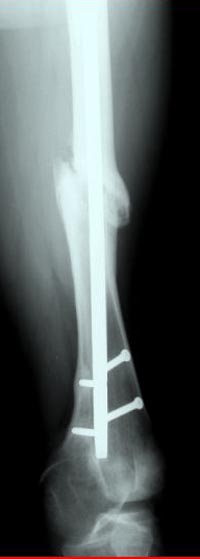

Лечение бедра - ургентное оперативное лечение антеградным с минимально рассверливанием, фиксацией с минимальным диаметром штифта и плюс irrigation and debridment и с закрытием поперечной до 10 см раны на уровне перелома в день поступления.

После трех дней начались выделения из ран которые промывалась в палате и рана постепенно закрылась в течение нескольких месяцев. Эмпирически получал 6 недельний курс антибиотика Vancomycin внутривенно.

Снимки представлены: 1 мес; 3 мес; 1 год; 2 года, предоперационные и ротационная КТ грамма